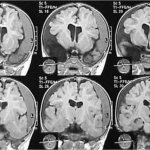

Children with microcephaly must be consulted by a geneticist to identify concomitant hereditary diseases. In order to determine the degree and prognosis, it is also important to conduct a full instrumental examination: ultrasound of the brain (neurosonography), electroencephalography (EEG), radiography of the skull, as well as computed and magnetic resonance imaging (CT and MRI).

If the diagnosis in newborns is confirmed, it is recommended to conduct a comprehensive examination using MRI, neurosonography and x-ray examination of the child’s brain.